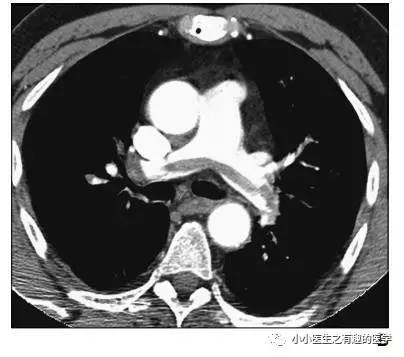

增强CT对比,一目了然。

上面的病人,增强CT放大了。

再来一个

很明显:扯蛋肺栓塞。